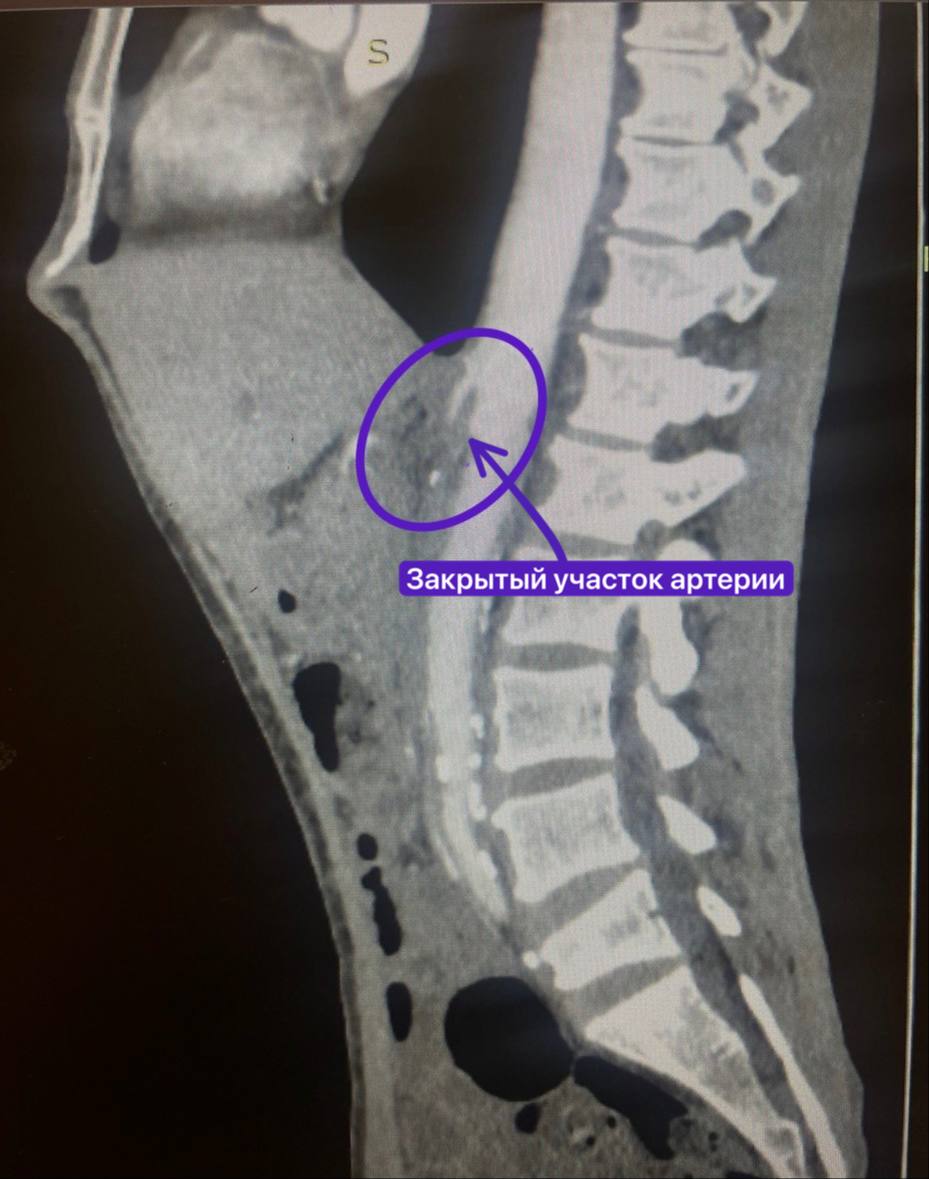

Вскоре пациент обратился в РКБ, где ему диагностировали полную закупорку верхней брыжеечной артерии из-за атеросклероза. Стандартная операция по установке стента оказалась невозможной – артерия была полностью перекрыта.